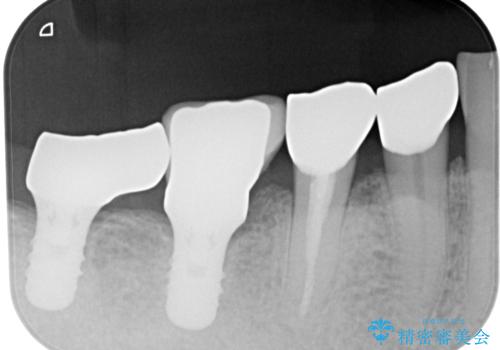

再度詰め物での処置を行うと引き続き欠けるリスクが高いため、高強度のフルジルコニアクラウンにて補綴治療を行うこととしました。

フルジルコニアクラウンは高強度であるため、クラウンの破損リスクは低減されましたが、失活歯(神経を取り除いた)では歯根破折リスクが高いとされており、抜歯の可能性が高まるため適用されません。